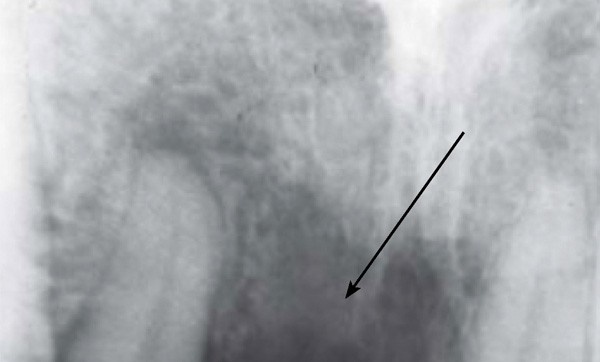

En termes de propriétés physiques, le PEEK présente de nombreux avantages. Sa densité et son module d’élasticité sont proches de ceux du tissu osseux. Il possède toutefois une limite de taille, puisqu’il est radio-transparent, ce qui complique considérablement l’analyse des clichés radiographiques pris en phase postopératoire (fig. 2) [5].